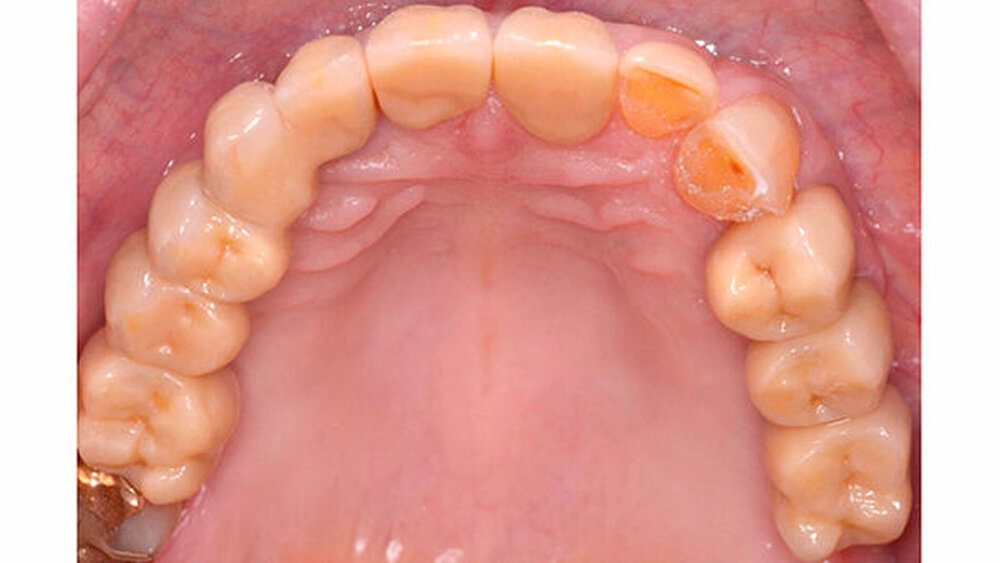

Dr. Sebastian Schwindling (Universität Heidelberg) ist Young-Esthetics-Preisträger 2017. Sein Fall ist komplex: die Gesamtrehabilitation eines parafunktionell vorgeschädigten Gebisses. "Selbst erfahrene Zahnärzte würden sich damit nicht leicht tun", heißt es aus der Jury. Hier stellt der Preisträger seine Arbeit vor.